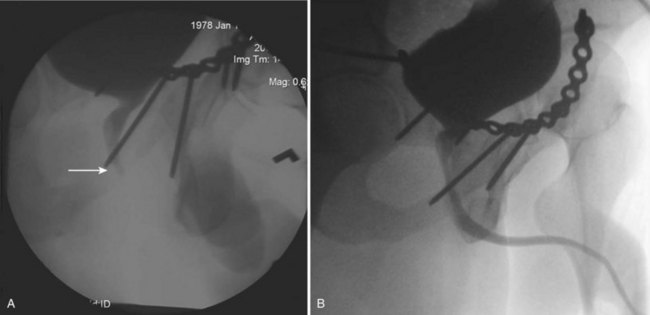

Increasingly, patients with pelvic ring fracture undergo early surgical fixation by orthopedists to decrease bleeding, improve healing, and speed ambulation (Connor et al, 2003). Although orthopedists frequently suggest that a suprapubic tube not be placed if anterior pubic hardware is used in pelvic fracture repair because of concern that the suprapubic tube will lead to hardware infection (Patterson, 1995), the authors and others (Borrelli and Brandes, 2004; Bepple et al, 2007) have repeatedly found that suprapubic cystostomy can safely be used without complications throughout the course of care (Fig. 88–17 on the Expert Consult website).

The authors use a large-bore (24 Fr) Foley catheter placed high in the bladder and tunneled through the skin as high as possible on the lower abdominal midline to keep the tube away from the plated symphysis.

An attempt at primary realignment of the distraction with a urethral catheter is reasonable in patients whose condition is stable (Elliott and Barrett, 1997), either acutely or within several days of injury. The authors prefer a simple technique consisting of passage of a coudé catheter antegrade from an anterior cystotomy to the urethral meatus, then tying it to another catheter that is drawn back into the bladder. A variety of more elaborate approaches have been described, frequently with retrograde and anterograde flexible cystoscopes (Follis et al, 1992; Routt et al, 1996; Elliott and Barrett, 1997; Porter et al, 1997; Asci et al, 1999; Mouraviev et al, 2005, Hadjizacharia et al, 2008), although the authors have observed that prolonged endoscopic realignment attempts risk infection of the pelvic hematoma (Morey et al, 1999) and thus cannot be recommended.